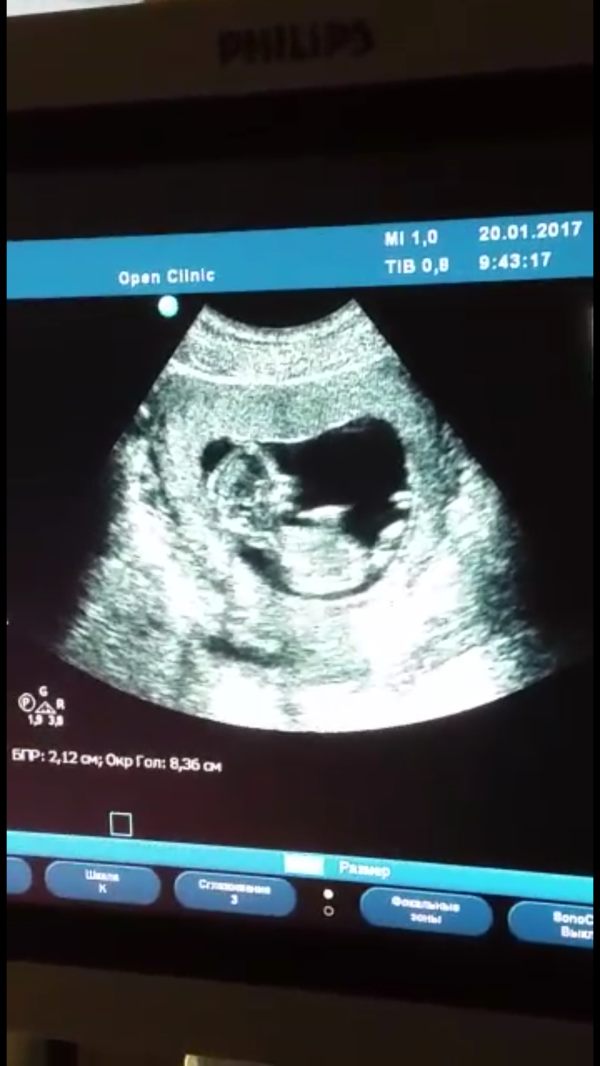

Были сегодня на 🔬первом скриниге🔬!!!

Как же долго мы ждали этот день, и как одновременно переживали. Но все хорошо, все отлично 🖒🖒 рыбка наша плавает, сказали очень активный ребеночек😊😊 ну он такоооой сладкий, ручонки, ноженьки, боже мой такой кроха!!! тьфу тьфу тьфу 💦💦💦 хоть я ещё и не чувствую ничего, но в такие моменты понимаешь, что ты не одна, что целых 7см чистого счастья находится у тебя в животике😍😍

@mama_papa_sin это я скриншот с видео сделала, муж сидел снимал на видео)))на память ))) разрешили, конечно😊😊